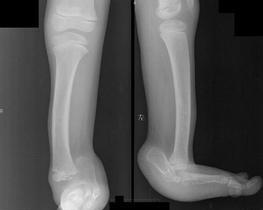

先天性肌缺如(congenital absence of muscles)临床上比较少见,是由于胎儿本身发育异常,或因在宫内受到机械阻碍所致。常表现为单块肌肉部分或全部缺如,也可表现为某一组肌肉的缺如。如果缺如的肌肉不能被其他正常肌肉所代偿,则可能出现畸形。